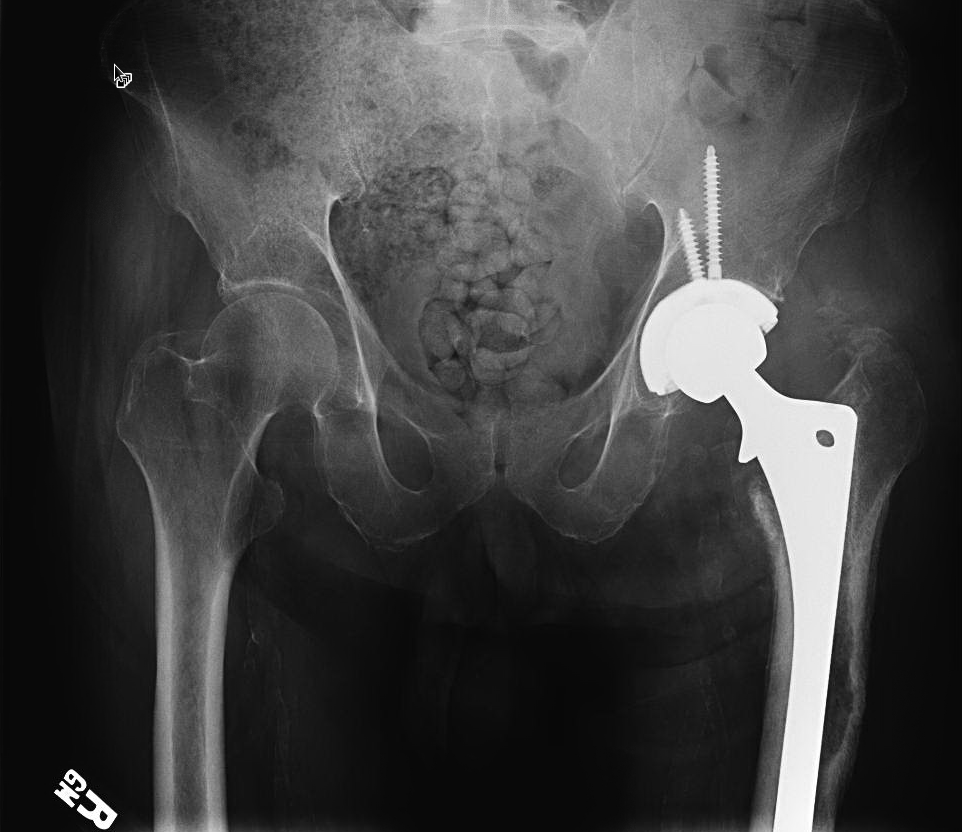

This patient had had a hip replacement operation in order to treat a hip fracture in Guadalajara, Mexico. He was living with his daughter in the US, still unable to walk, more than a year after his fracture.

Xray appearance and blood tests indicated a low grade infection of the left hip prosthesis. A needle aspiration of the hip joint showed that he was infected with Streptococcus spp bacteria.

In this particular case, it was fortunate that the entire implant came out easily together with the cement mantle. In many cases it is necessary to perform an extended trochanteric osteotomy to remove the implant (see another case description below).

Patient became able to walk and stayed clear of infection when I last saw him, more than 3 years after surgery.